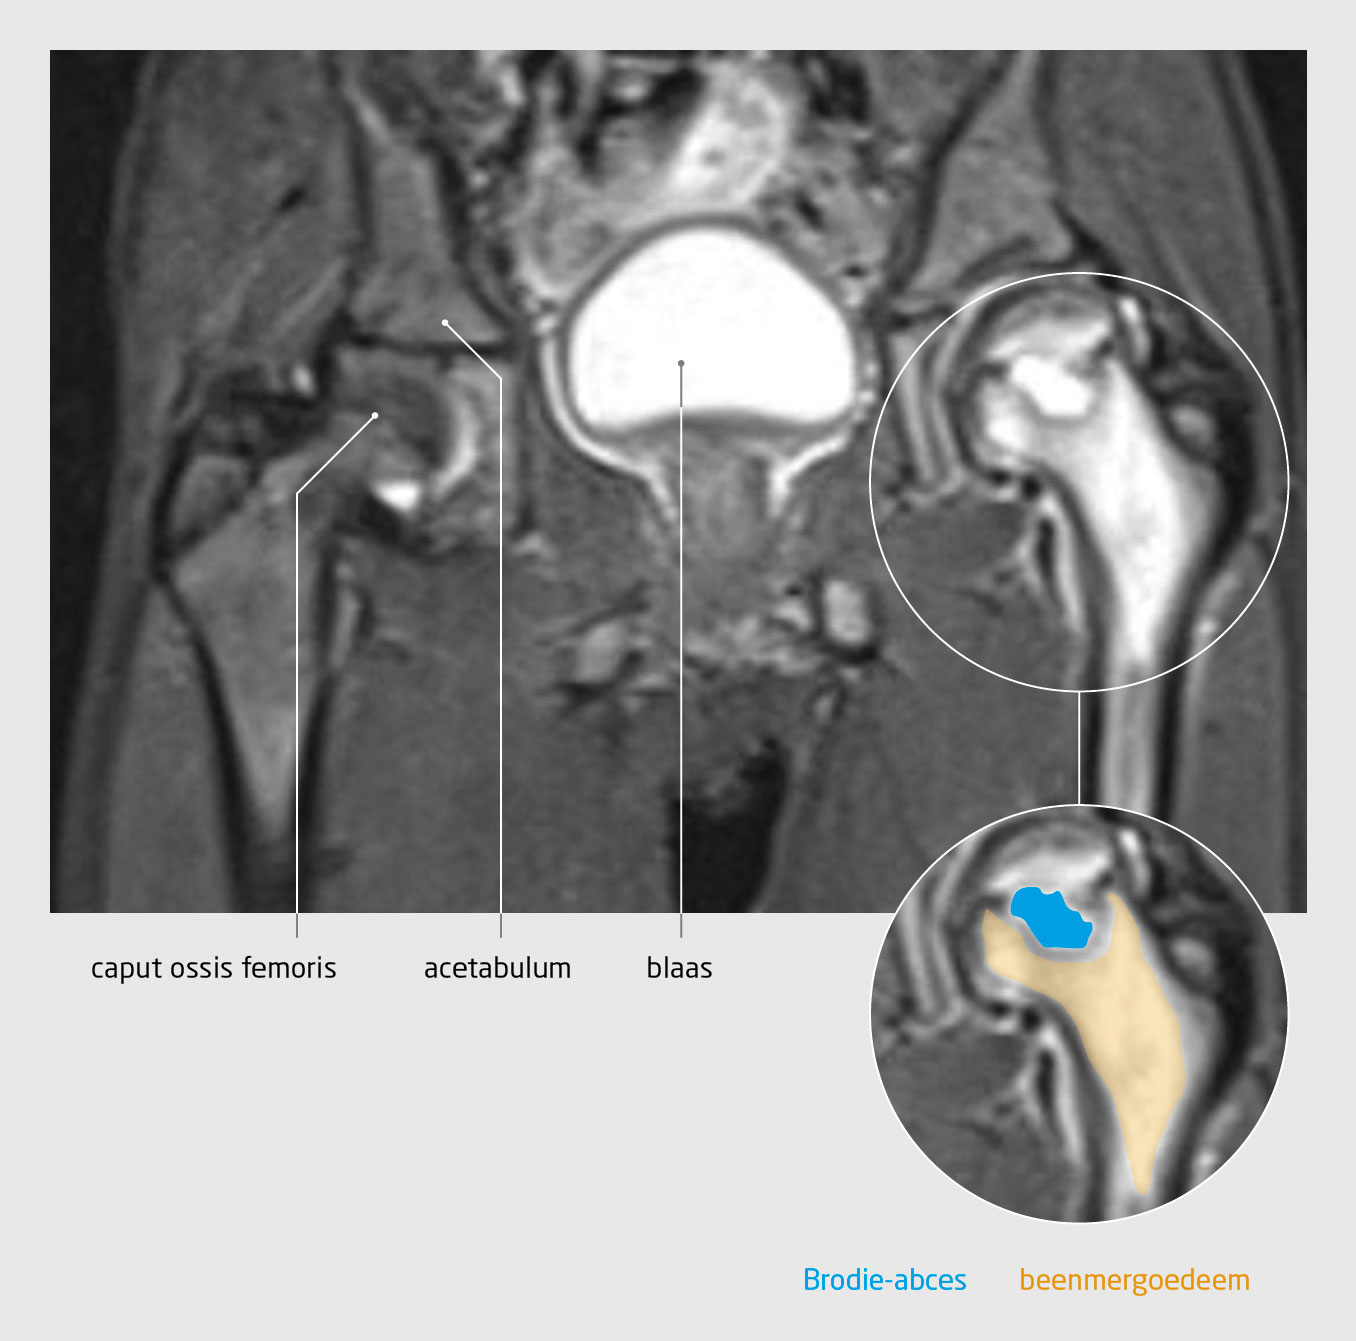

Wij adviseerden om de heup te ontlasten. In de daaropvolgende maanden verslechterde echter zowel het klinisch als het radiologisch beeld, met een verdere afplatting en sclerose van het caput ossis femoris (figuur 3). Op het preoperatieve artrogram werd een ‘hinge abduction’ gezien – een gevolg van de ziekte van Perthes waarbij het craniolaterale deel van het caput ossis femoris uitsteekt buiten het acetabulum. Mede gezien de relatief late presentatie besloten wij een correctie-osteotomie van het proximale femur te verrichten om de positie van het femur ten opzichte van het acetabulum te verbeteren.

Progressie en behandeling van de ziekte van Perthes

Figuur 3 | Progressie en behandeling van de ziekte van Perthes

Röntgenopnames van het bekken. (a) Ondanks ontlasten van de heup is een half jaar na de diagnose verdere afplatting en sclerose van het caput ossis femoris opgetreden. (b) Status 3 maanden na correctie-osteotomie van het linker proximale femur, waarbij de positie van het femur ten opzichte van het acetabulum is verbeterd.

Bij controle 3 maanden na de operatie liep patiënt zonder pijn en was op de controlefoto een geconsolideerde osteotomie te zien (zie figuur 3). Wij zullen de controles vervolgen totdat patiënt is uitgegroeid.